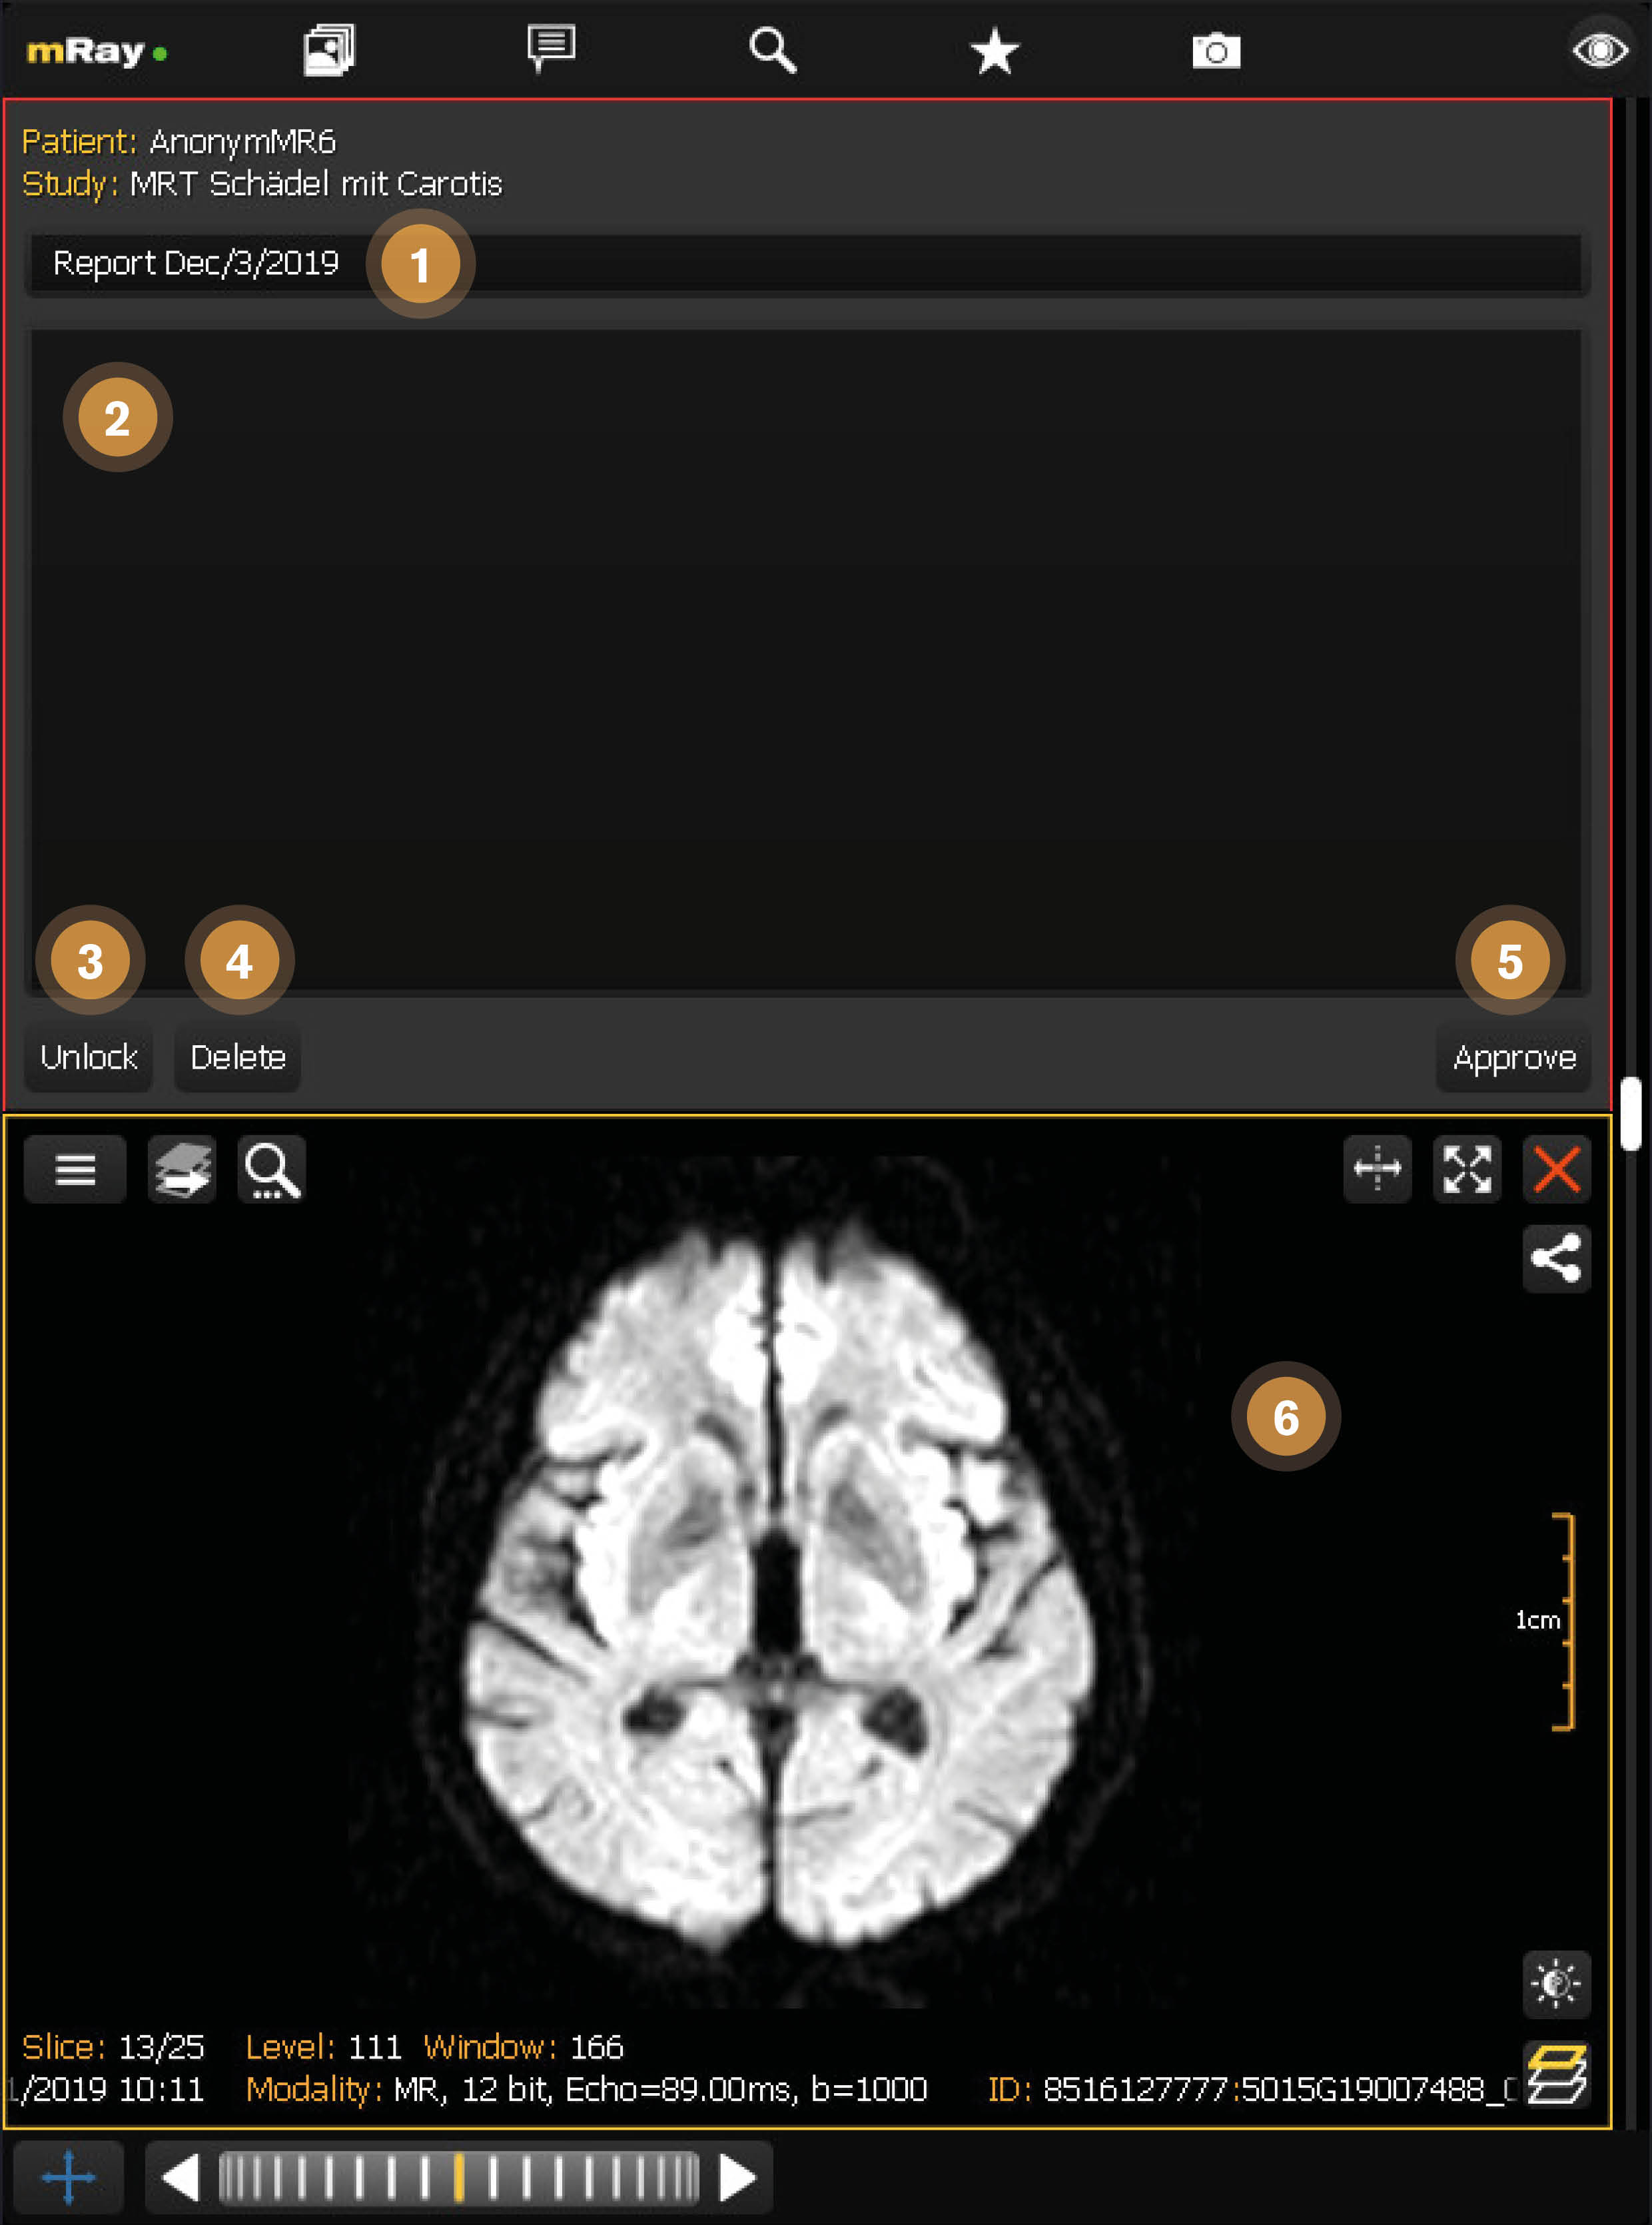

12.3. Entwurf Bearbeitungsansicht

Nachdem ein Entwurf erzeugt wurde, öffnet er sich direkt neben der dazugehörigen Studie. Die Patienten- und Studieninformationen werden automatisch ausgefüllt. Der Berichttitel wird standardmäßig auf das aktuelle Datum gesetzt, kann jedoch bearbeitet werden. Solange der Bericht geöffnet ist, wird er für andere Benutzer gesperrt, damit sie ihn nicht bearbeiten könnten. Dadurch werden Konflikte durch parallele Bearbeitung des selben Berichts vermieden.

-

Berichttitel: Der Titel für den Bericht. Ist vorausgefüllt mit dem aktuellen Datum.

-

Berichtinhalt: Der Inhalt für den Bericht z. B. die Diagnose oder andere klinische Informationen.

-

Entwurf entsperren: Entsperrt den Entwurf damit andere Nutzer daran weiterarbeiten können.

-

Entwurf löschen: Löscht den Entwurf für alle Benutzer.

-

Entwurf freigeben: Gibt den Entwurf frei und erzeugt daraus den finalen Bericht. Der Bericht kann anschließend nicht mehr verändert werden.

-

Zugehörige Studie: Zeigt die verknüpfte Studie an.